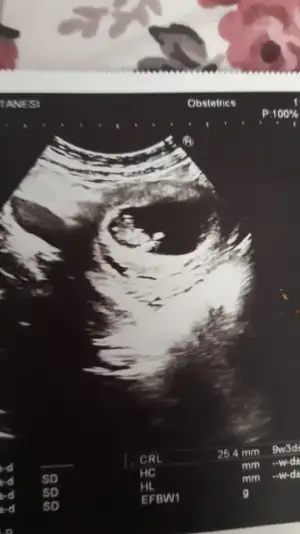

Dik canım parelek olsa kız derdim tabi benimki tahmin inşallah gönlünüzdeki olur işk bebekmiKızlar doktor çok erken dedi ama ben videoya çektim bugün burada nubu belli 11+0 bugün sizce nedir cinsiyet

Erkek gibi12 haftalık görüntü bize de bakarmısınız

Erkek diyorumKızlar doktor çok erken dedi ama ben videoya çektim bugün burada nubu belli 11+0 bugün sizce nedir cinsiyet

Kaç haftalıkMrb bu arkadaşımın ultrason görüntüsü bakar mısınız